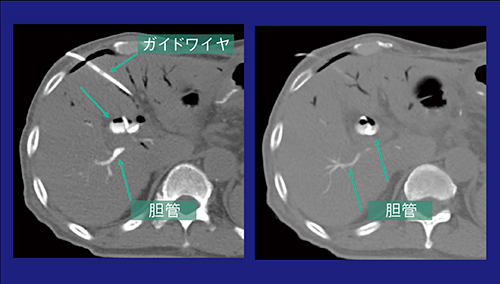

1)ドレナージ

症例2は,70歳代,男性,閉塞性黄疸を呈した膵頭部がん術後で,挙上空腸の拡張と通過障害があり,再発腫瘍が疑われた。いったんENBD(endoscopic nasobiliary drainage:内視鏡的経鼻胆管ドレナージ)チューブで症状は改善したが,患者の負担を考慮してドレナージルートの変更が検討された。経皮ルートのPTBD(percutaneous transhepatic biliary drainage:経皮経肝的胆管ドレナージ)が検討され,超音波ガイド下のPTBDを行ったが,胆管気腫のため穿刺は困難だった。そこで,ENBDチューブより空気を注入して,肝内胆管と挙上空腸を拡張し,CT透視下でドレナージを施行した。術前CTを確認してルートを決定し,肝内胆管への穿刺を確認後,造影剤を注入。胆管の位置を確認後,ワイヤを挿入してPTBDを留置し,内瘻化に成功した(図5)。

図5 症例2:CT透視下で肝内胆管の穿刺を確認